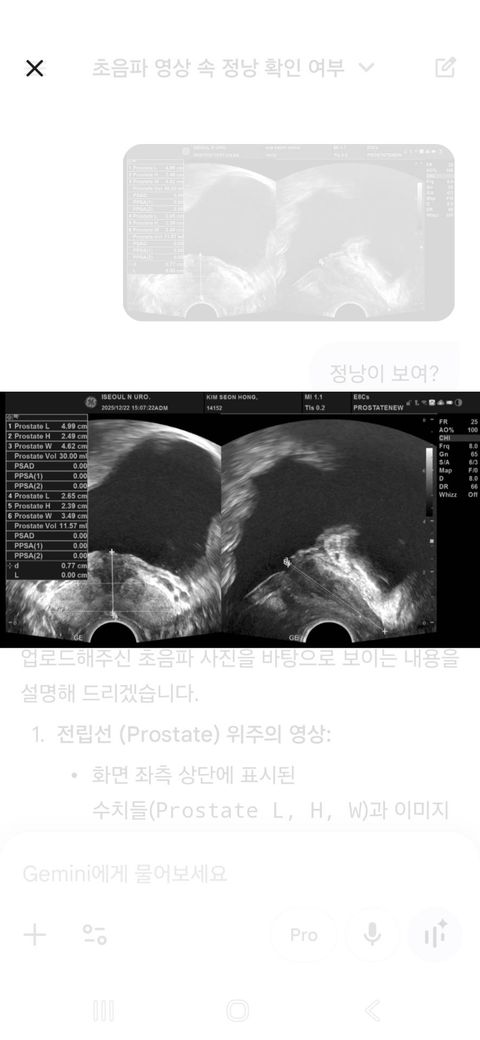

전립선 및 정낭 초음파 질문드립니다.

전립선 초음파를 했습니다.

선생님이 보시곤 정낭이 비대하다고

정낭염과 전립선염이라고 하시면서 항생제 처방을 하셨는데? 초음파에서 염증 소견이 확실하게 보이는지? 궁금합니다.

• 1번 째 사진

초음파를 통해 전립선염을 진단하는 것은 아닙니다. 전립선염이 의심될 때 전립선 초음파를 시행하는 것은 전립선염에 의한 합병증으로 농양 등의 발생을 확인하는 것이며 전립선 폐색을 유발할 수 있는 구조적인 문제가 있는지 확인하는 것에 주목적이 있습니다. 전립선염은 초음파만으로 진단하는 것이 아니며 혈액검사나 정액검사 임상 증상을 종합하여 판단하게 됩니다. 올려주신 사진만으로 전립선염 여부를 알기는 어려우며 농양이나 구조적인 이상은 없는 것으로 판단할 수 있습니다.